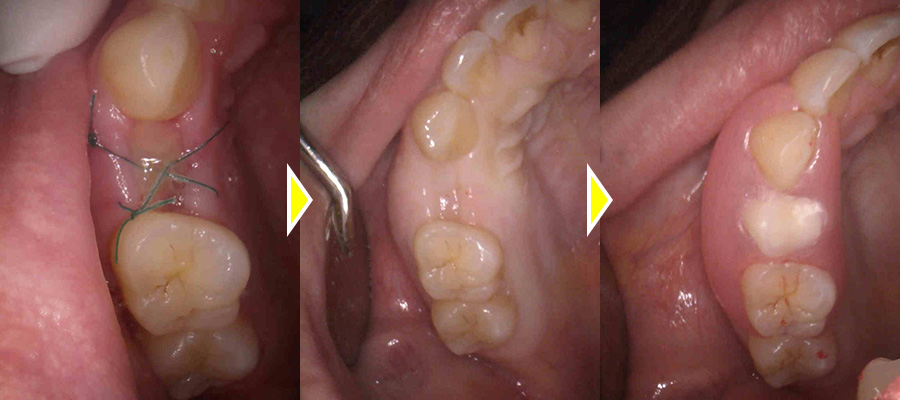

2回法により施術を、行い、3ヶ月後には歯茎も綺麗に回復しておりました。

二次オペを行いしっかりとした固定も得られていた為、型取りを2度行い上部に歯を作成しました。

上部構造(人工歯)の装着・治療完了

術後は欠損部位の見た目の改善により、審美的に大変満足していただき、また、機能的な面でも硬いものもしっかり噛むことができ、機能的な面でも大変満足していただきました。